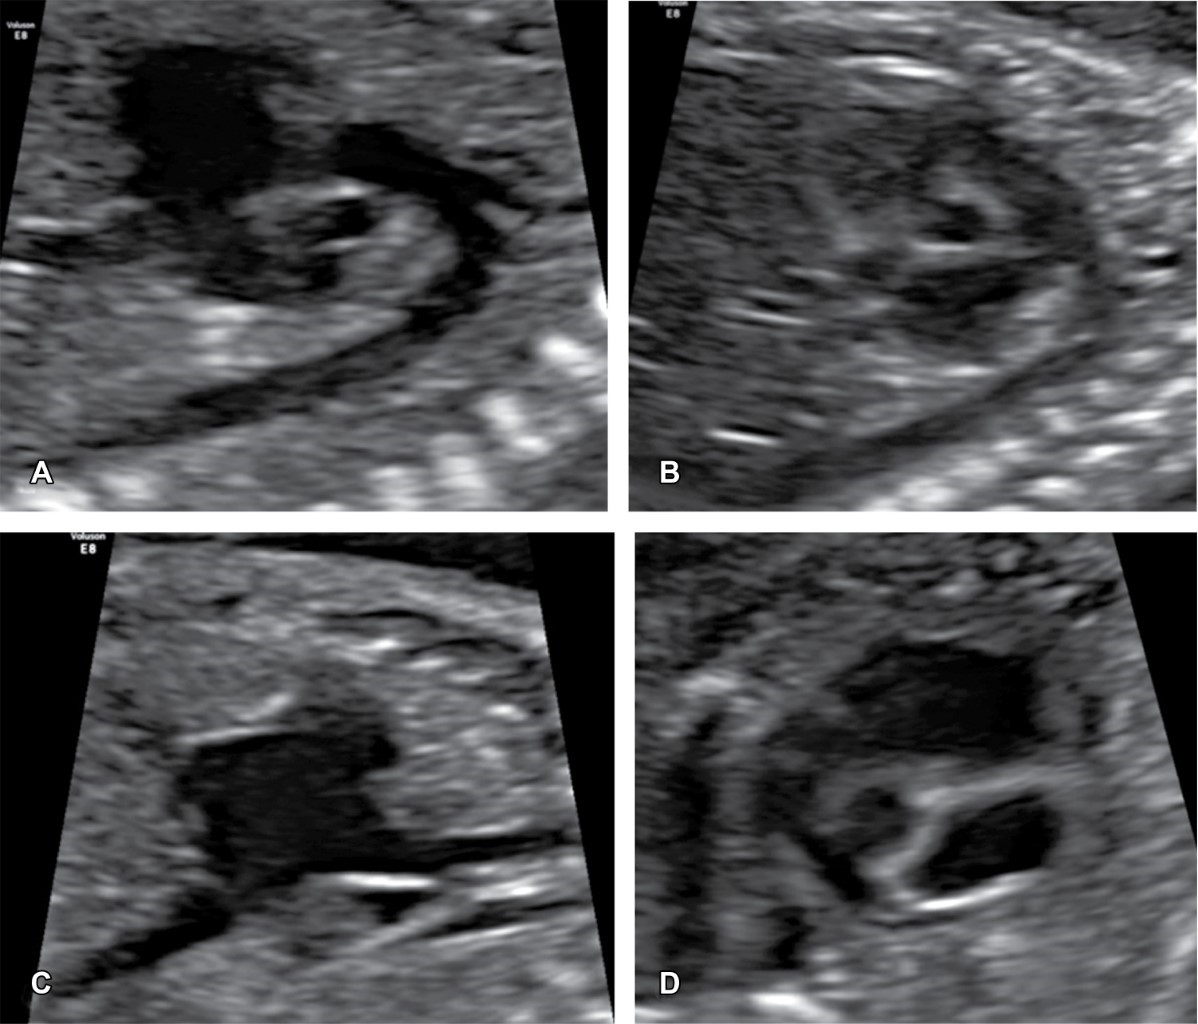

Figure 2